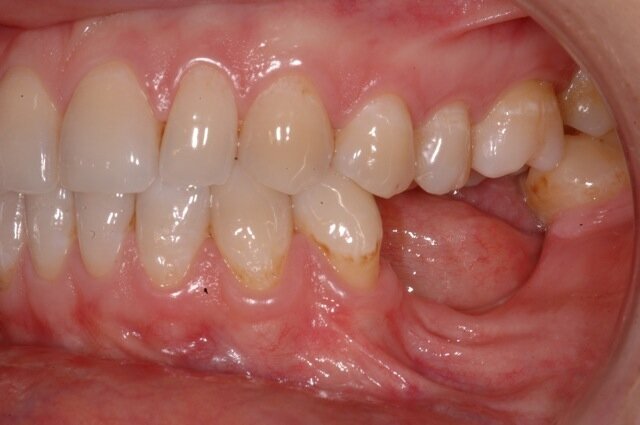

Una paziente di 35 anni si presentò alla nostra attenzione per risolvere un edentulismo parziale nella zona mandibolare inferiore sinistra conseguente all’estrazione traumatica degli elementi 35 e 36 in età scolare (Fig. 1). La paziente all’esame obbiettivo dimostrava un ottima igiene orale con un indice di placca del 7% e un indice di sanguinamento del 5%. L’esame clinico della zona traumatizzata evidenziava una lesione di terza classe di Seibert6 laddove il deficit osseo era caratterizzato da una deficienza nei tessuti duri e molli sia in senso orizzontale che in senso verticale. Risultava significativa anche la scarsa quantità di gengiva cheratinizzata a ricoprire la cresta residua, quantificabile in una banda larga non più di 2 mm (Fig. 2). Una volta eseguita la terapia causale atta a rimuovere il biofilm presente e a preparare la paziente per l’intervento, si procedette a eseguire un esame Cone Beam per approfondire la conoscenza dell’anatomia locale e procedere con un piano di trattamento adeguato alla soluzione di questa problematica.

Nella rx si vedono i due impianti con le viti di guarigione ad integrazione avvenuta. In figura 16 si nota l’ottimo aspetto dei tessuti peri-implantari con una adeguata quantità e qualità di gengiva cheratinizzata e le susseguenti corone in metallo ceramica successivamente cementate su due perni moncone in titanio fresati in laboratorio. Nelle foto successive si possono evidenziare le differenze dalla situazione iniziale (Fig. 17) a quella finale, in questo caso una foto di follow up a 48 mesi dalla finalizzazione del caso (Fig. 18). La rx a quattro anni dalla finalizzazione protesica evidenzia una situazione di perfetta stabilità, una cresta ossea ben mineralizzata ed un livello osseo inalterato dal momento della consegna del manufatto protesico definitivo (Fig. 19).